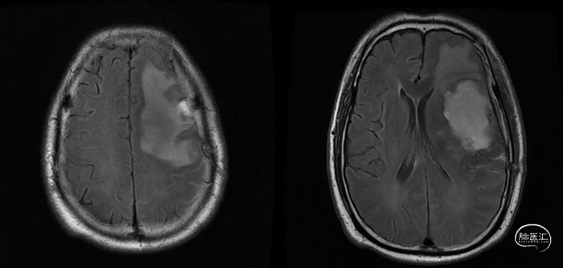

肿瘤电场治疗16天,RT后1月(2020-07-22):图示。

放疗后8月(2021-03-17):如视频和图像。

术后5周开始实施标准的新STUPP方案的辅助治疗,即在同步放化疗后,辅助替莫唑胺化疗的同时使用了电场治疗。目前生存25月,且临床和影像学表现均提示稳定,未见复发迹象。期间,在放疗后7月时复查MRI提示异常FLAIR信号区增大,经我院MDT讨论,考虑到强化信号减轻,无明显占位效应,患者无症状体征,考虑是治疗后水肿,非进展,故继续按原方案治疗。放疗后17月复查MRI出现术区边缘局部强化范围稍增大,但PWI示强化区局部呈低灌注且未见弥散受限表现,MDT讨论考虑为假性进展,继续原方案治疗。后续复查MRI强化范围减轻,证实了MDT的判断证实疾病稳定。患者生存时间已达25个月。全程安全顺利,仅出现一过性轻度皮肤反应。

辅助TMZ治疗过程中每2-3月复查MRI。治疗中曾出现水肿范围增大,尽管有部分区域弥散受限和MRS异常及血流量增加,但是临床症状未加重,仍继续原方案治疗,后续监测PWI显示病变区灌注减低。提示持续肿瘤电场治疗可以使病变长期稳定。此患者每天佩戴肿瘤电场治疗时间接近22小时,中间出现头皮发红和小水泡,经局部外用皮质类固醇和外用抗生素,暂停2天治疗恢复。至今随访25月稳定。说明肿瘤电场治疗联合TMZ治疗较单TMZ治疗明显延长胶质母细胞瘤患者PFS及OS,临床应积极推广使用。